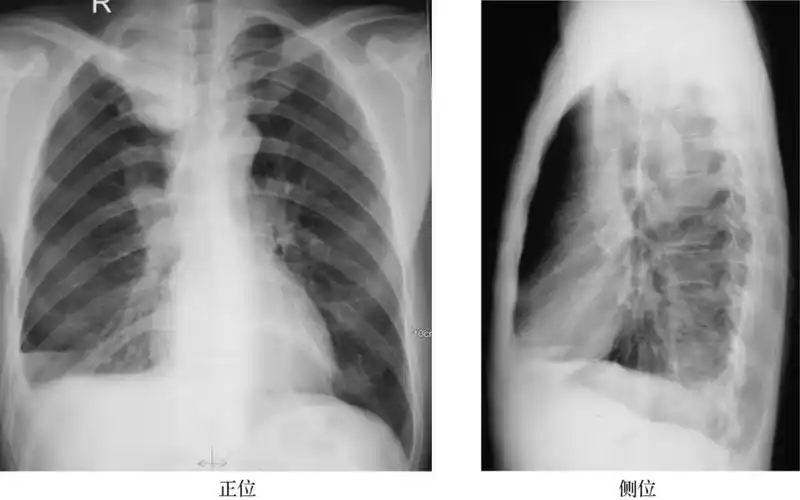

典型的肺癌

肺癌的线表现